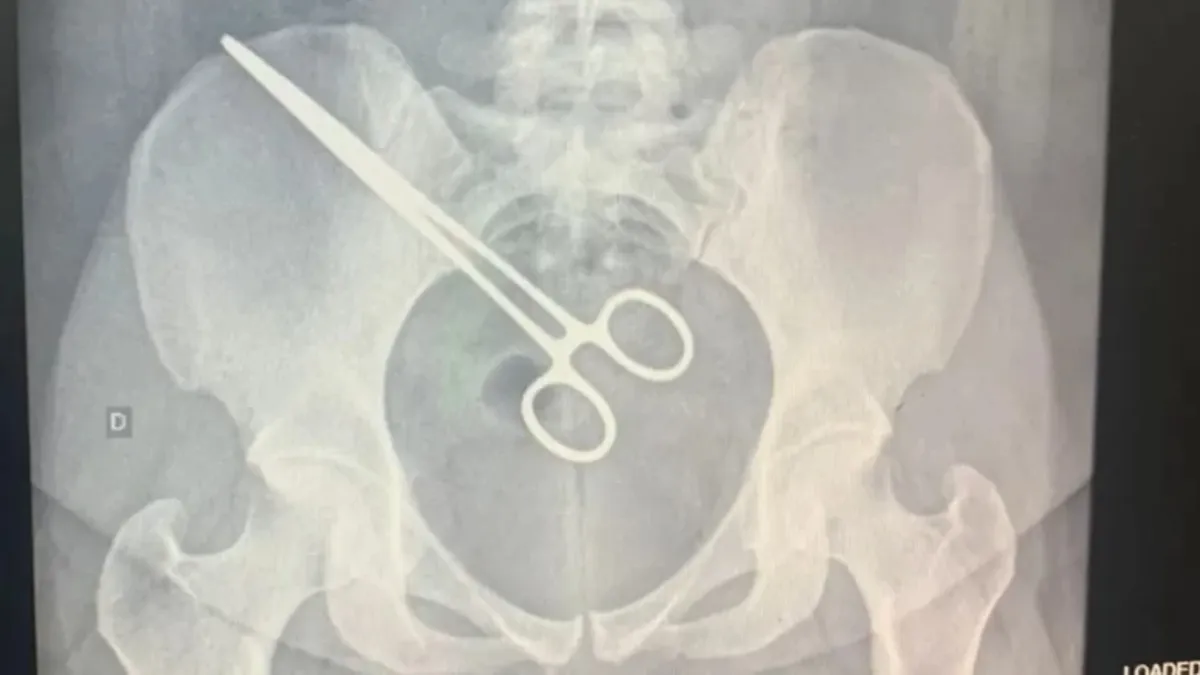

A mulher, ao tomar conhecimento, se dirigiu à Santa Casa, onde confirmaram a presença da pinça em sua região pélvica. Vale ressaltar que a cirurgia que resultou nessa situação ocorreu no mesmo hospital, em setembro.

Diante desse cenário, a mulher foi submetida a uma nova cirurgia para a remoção do objeto. A direção da Santa Casa de Araçatuba garante que “o hospital possui protocolos específicos para que os procedimentos cirúrgicos sejam realizados com segurança para os pacientes”.